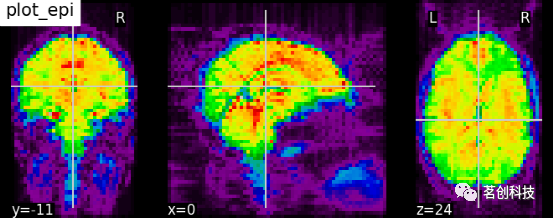

plot_epi:用函数plot_epi绘制EPI或T2*图像。

# 导入图像处理工具

from nilearn import image

# 计算函数图像的voxel_wise平均值

# 将函数图像从4D降维至3D

mean_haxby_img = image.mean_img(haxby_func_filename)

# 可视化均值图像(3D)

plotting.plot_epi(mean_haxby_img, title="plot_epi")